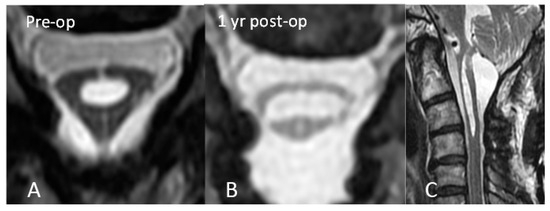

In order to address the postoperative adhesive arachnoiditis, a third surgery was performed. This surgery involved laminoplasty of C3–4 and extensive duroplasty from the suboccipital region to the C4 level. During the surgery, a thick arachnoid band was discovered. This band tethered the cord at the C2 level, confirming the presence of the delta cord sign. After separation of the arachnoid band, the syrinx collapsed, and the arachnoid space was no longer obstructed (Figure 3). After 1 year of postoperative follow-up, the syrinx collapsed, and an improvement of the edematous change in the spinal cord was observed (Figure 4). In addition, the patient’s functional status improved, with his mJOA score increasing from 10 to 11 and his Barthel Index score increasing from 50 to 60. Thus, he was able to walk with the assistance of a cane and perform the majority of his daily tasks, albeit with some dependency. He continued to experience residual paresthesia in his upper limbs and left lower limb.

Figure 4.

(A) Delta cord sign and (B) 1 year after surgery. The shape of the cord became more oval. (C) Sagittal view 1 year after surgery. Decreasing diameter of the syrinx and absence of edematous change were observed.